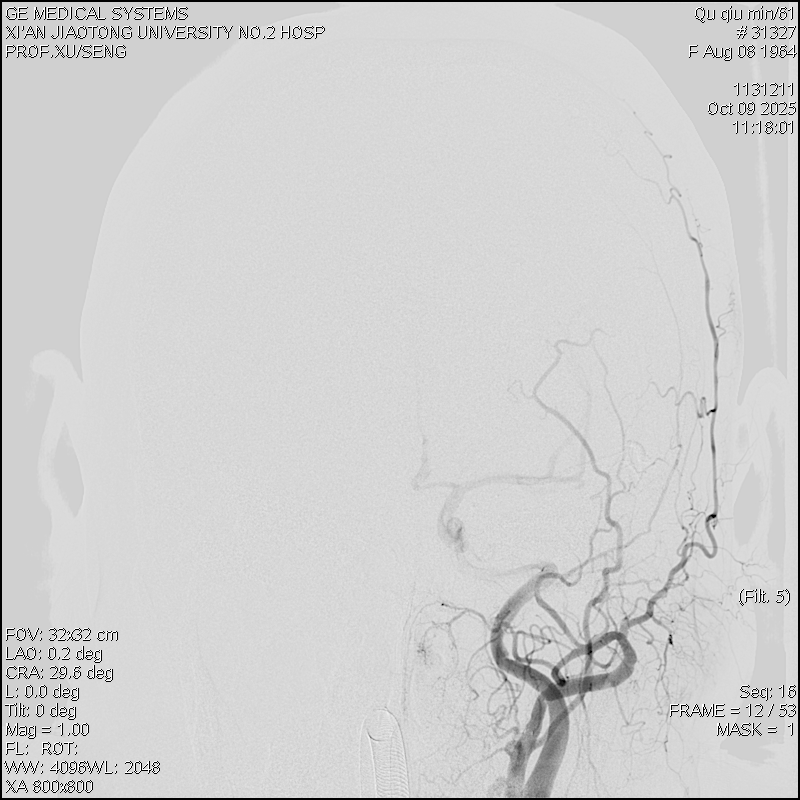

团队结合患者病史、影像学检查以及使用激素后加重的特征,讨论后认为动静脉瘘的可能性较大。但全脊髓造影并未发现硬脊膜动静脉瘘,那么,这个瘘会不会在颅内,只是朝脊髓引流了。根据这个猜测,许刚副主任医师团队为患者进行了全脑血管造影,初步的血管造影并未发现明显病灶。团队并未轻易放弃,又对可疑的各分支血管进行了超选择性造影。最终发现了该患者为脑膜中动脉及枕动脉脑膜支供血的一个非常细小的瘘口。该瘘位于岩骨脊,向下朝脊髓引流,不仔细研究很可能发现不了。

明确诊断后,许刚副主任医师、僧志远主治医师运用介入技术成功对该瘘口进行了栓塞,栓塞术后次日患者的双侧下肢感觉及运动功能就明显好转。一周后患者转当地医院继续康复治疗。

术前颈外造影正位